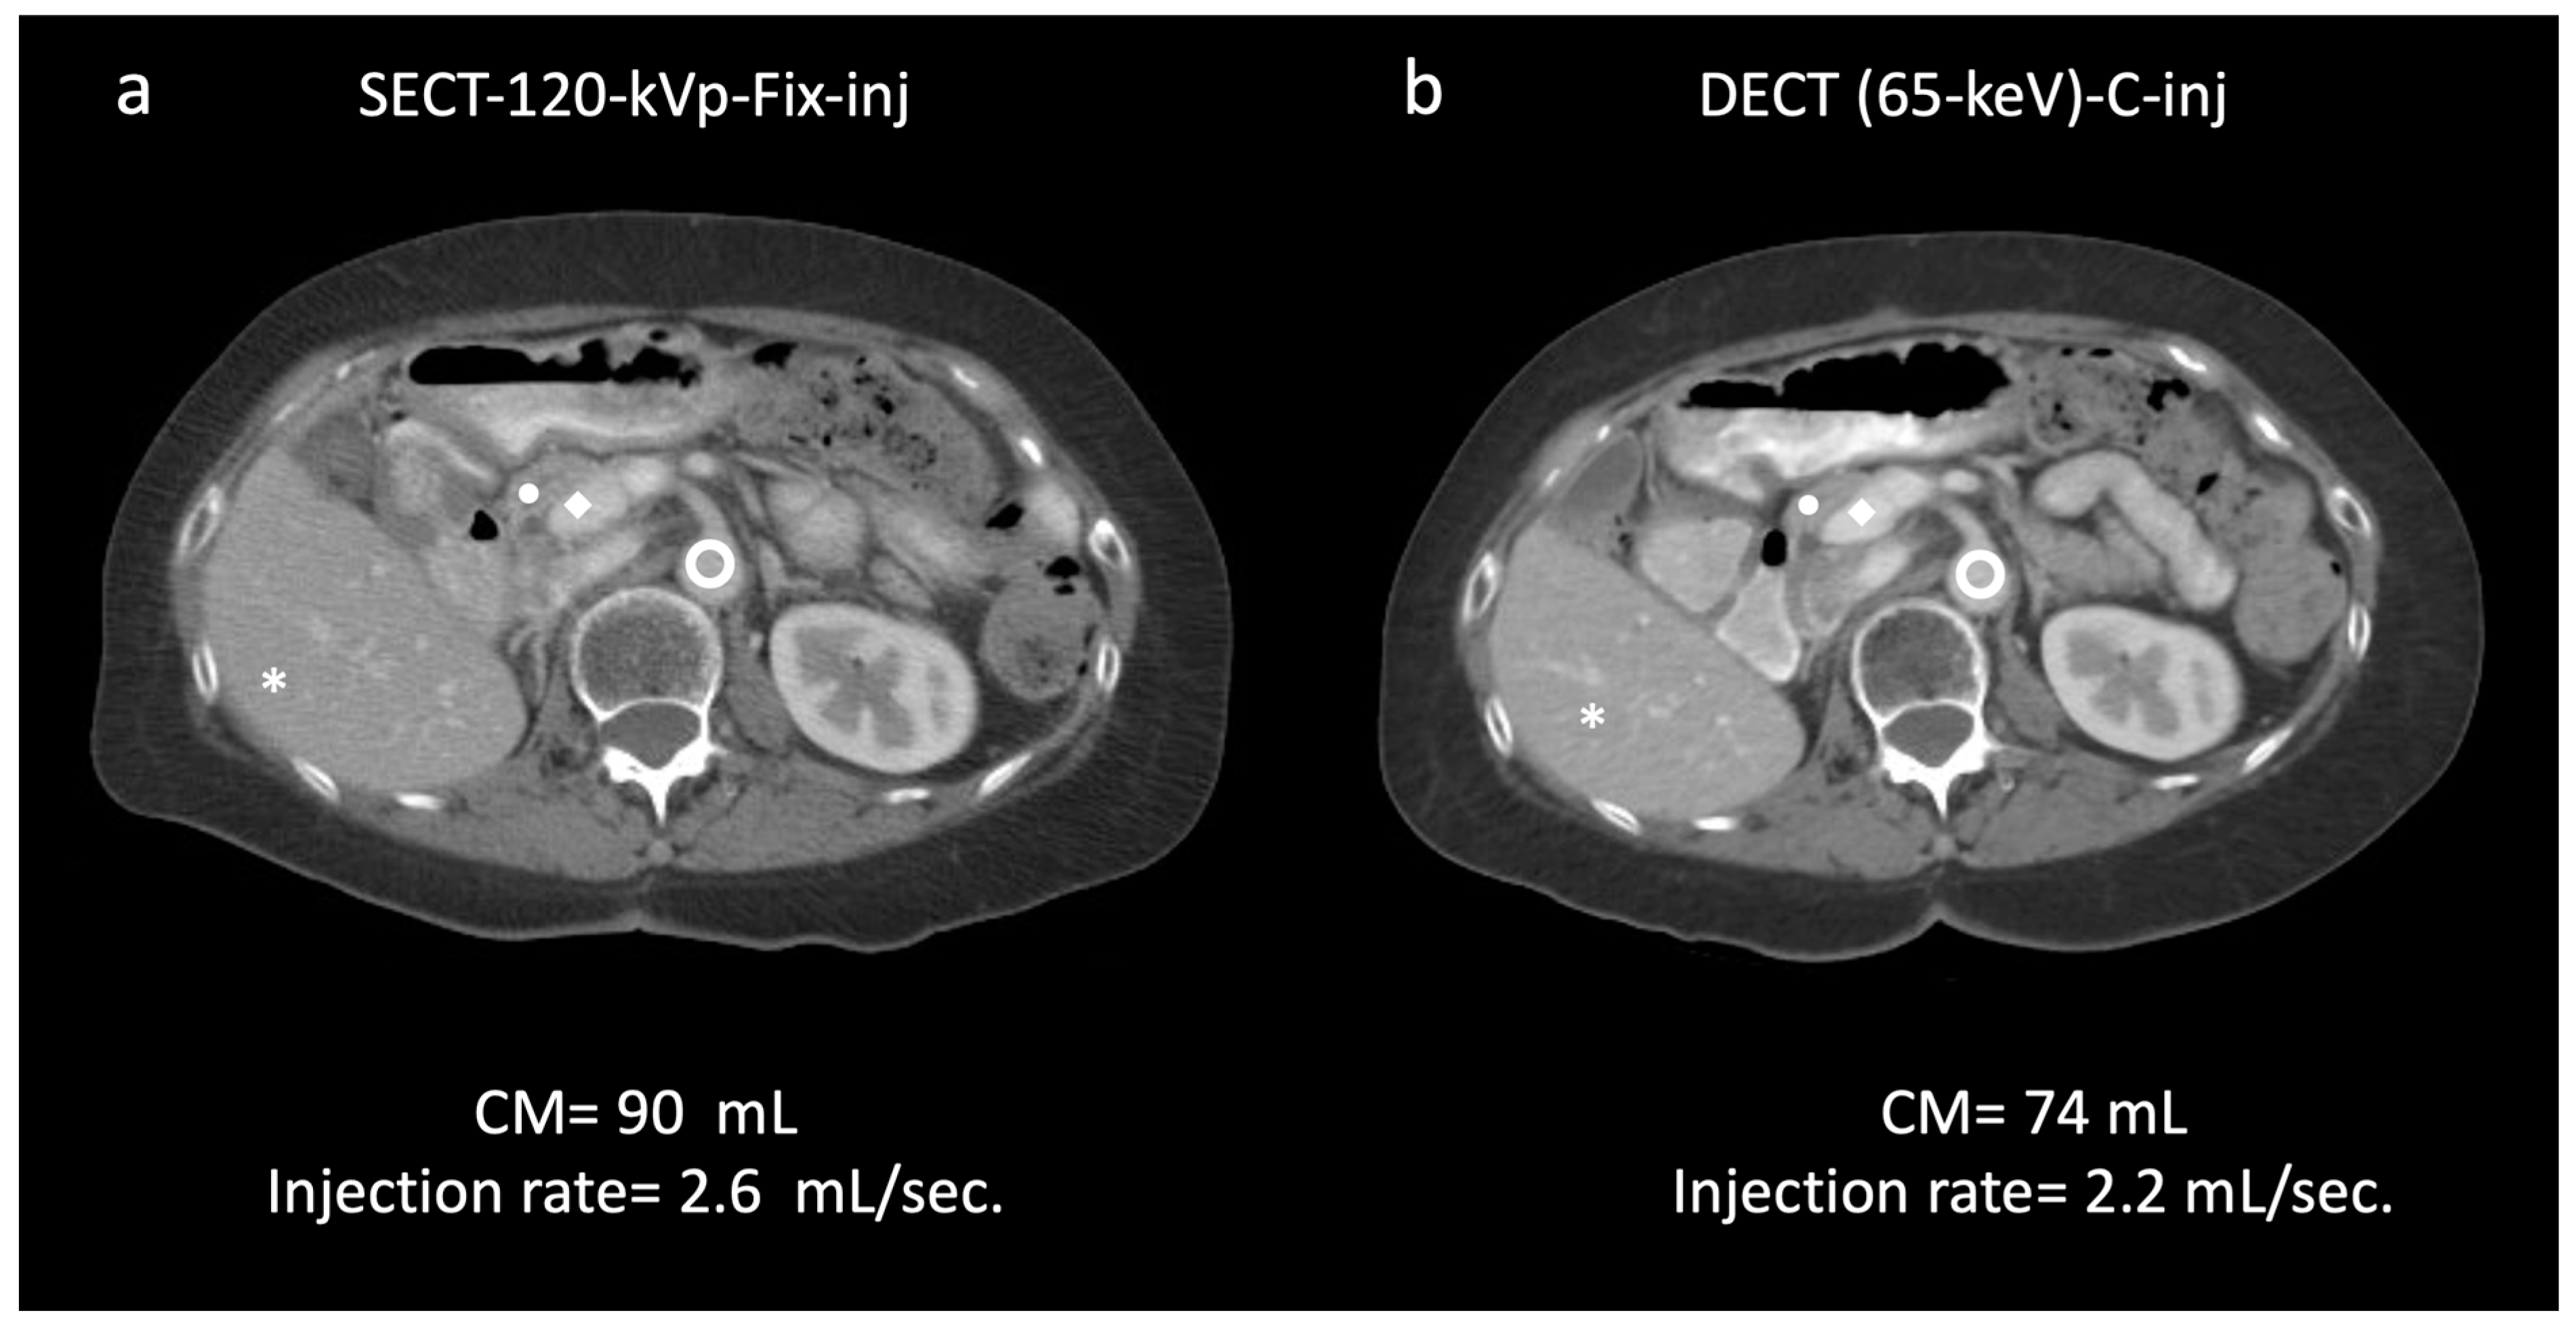

aorta, 149.9/23.5; ◆ portal vein, 162.0/25.6 (a). In the same patient, a 65 keV virtual monochromatic image reconstructed from dual-energy CT (DECT) acquisition with customized injection (b) resulted in administration of a reduced volume of contrast media and injection rate (74 mL; −17.7%; 2.2 mL/s; −15.3%, respectively) and yielded significantly higher values of attenuation/CNR: * liver, 128.7/30.7 (+12/36.4%); ● pancreas, 113.3/24.6 (+18.7/25.5%);

aorta, 149.9/23.5; ◆ portal vein, 162.0/25.6 (a). In the same patient, a 65 keV virtual monochromatic image reconstructed from dual-energy CT (DECT) acquisition with customized injection (b) resulted in administration of a reduced volume of contrast media and injection rate (74 mL; −17.7%; 2.2 mL/s; −15.3%, respectively) and yielded significantly higher values of attenuation/CNR: * liver, 128.7/30.7 (+12/36.4%); ● pancreas, 113.3/24.6 (+18.7/25.5%);  aorta, 186.6/32.7 (+24.4/39.1%); ◆ portal vein, 210.5/32.57 (+29.9/37.1%) (b). Subjectively, both readers rated the two scans as 5. DECT-65 keV-C-inj: dual-energy CT at 65 keV with customized injections; SECT-120 kVp-Fix-inj: single-energy CT at 120 kVp with fixed injections.

aorta, 186.6/32.7 (+24.4/39.1%); ◆ portal vein, 210.5/32.57 (+29.9/37.1%) (b). Subjectively, both readers rated the two scans as 5. DECT-65 keV-C-inj: dual-energy CT at 65 keV with customized injections; SECT-120 kVp-Fix-inj: single-energy CT at 120 kVp with fixed injections.

aorta, 149.9/23.5; ◆ portal vein, 162.0/25.6 (a). In the same patient, a 65 keV virtual monochromatic image reconstructed from dual-energy CT (DECT) acquisition with customized injection (b) resulted in administration of a reduced volume of contrast media and injection rate (74 mL; −17.7%; 2.2 mL/s; −15.3%, respectively) and yielded significantly higher values of attenuation/CNR: * liver, 128.7/30.7 (+12/36.4%); ● pancreas, 113.3/24.6 (+18.7/25.5%);

aorta, 149.9/23.5; ◆ portal vein, 162.0/25.6 (a). In the same patient, a 65 keV virtual monochromatic image reconstructed from dual-energy CT (DECT) acquisition with customized injection (b) resulted in administration of a reduced volume of contrast media and injection rate (74 mL; −17.7%; 2.2 mL/s; −15.3%, respectively) and yielded significantly higher values of attenuation/CNR: * liver, 128.7/30.7 (+12/36.4%); ● pancreas, 113.3/24.6 (+18.7/25.5%);  aorta, 186.6/32.7 (+24.4/39.1%); ◆ portal vein, 210.5/32.57 (+29.9/37.1%) (b). Subjectively, both readers rated the two scans as 5. DECT-65 keV-C-inj: dual-energy CT at 65 keV with customized injections; SECT-120 kVp-Fix-inj: single-energy CT at 120 kVp with fixed injections.

aorta, 186.6/32.7 (+24.4/39.1%); ◆ portal vein, 210.5/32.57 (+29.9/37.1%) (b). Subjectively, both readers rated the two scans as 5. DECT-65 keV-C-inj: dual-energy CT at 65 keV with customized injections; SECT-120 kVp-Fix-inj: single-energy CT at 120 kVp with fixed injections.